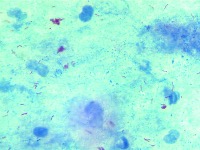

Medical Diagnostics: The "mtbs" model, presumably used to detect different manifestations of Mycobacterium tuberculosis (MTB), could be utilized in healthcare settings to assist healthcare professionals with identifying different classes of tuberculosis for proper treatment.

Research and Development: Scientists and researchers working on Tuberculosis-related studies can use this model to classify and analyze their data more easily, increasing the efficiency and speed of their work.

Public Health Monitoring: Government health departments and public health organizations could use this tool to identify trends and monitor prevalence of the different TB classes within the population from samples, enabling more targeted public health interventions.

Teaching Aid: Educational institutions teaching microbiology or pathology related courses can leverage this model to illustrate the different types/classes of MTB, enabling students to learn more effectively.

Pharmaceutical Companies: Drug development companies can utilize this model to assess the effectiveness of new treatments against various classes of MTB. The classes identified by the model can help in determining the efficacy of the drugs on respective strains.